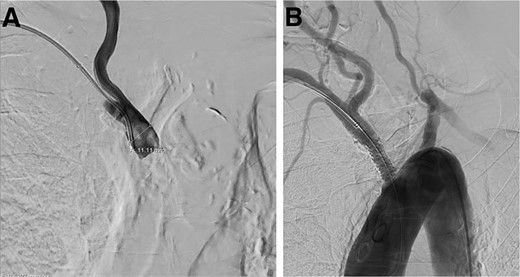

A cerebral angiogram demonstrated left common carotid occlusion (Fig. 1A) and the occlusion of the origin of the right brachycephalic trunk (Fig. 1B). Consequently, the left vertebral artery is the only cerebral vessel from the aortic arch filling anterogradely, resulting in retrograde flow to the brachycephalic trunk and of the right common carotid artery and right vertebral artery (Fig. 2A–D). The left internal carotid artery is filled from the left occipital artery, which is filled by the left vertebral artery. Intracranially the patient has the posterior communicating artery and the anterior communicating artery.

Digital subtraction angiogram demonstrating: (A) anterograde flow in the left vertebral artery and contrast going through the basilar formation. (B) Retrograde flow in the right vertebral artery. (C) Contrast reaching the right subclavian artery. (D) Anterograde flow in the right common carotid artery.